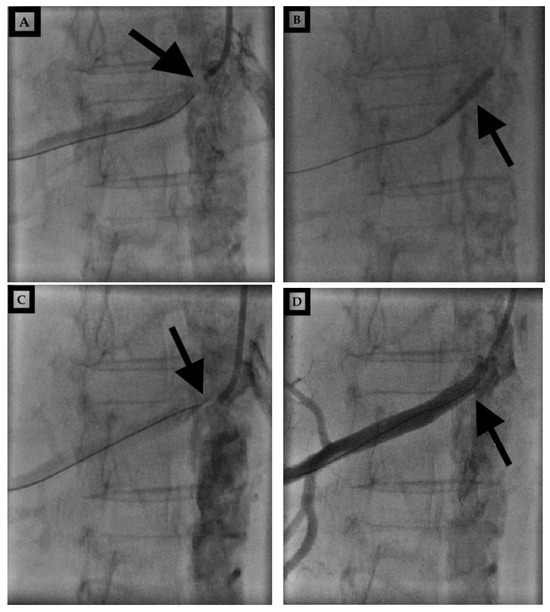

The patient sought a second opinion in another institution, where they stated that they could try PTA. An interventional radiologist from the second hospital performed PTA of the right renal artery and implanted a stent at the site of subocclusion (Figure 3), resulting in total renal function recovery. Three months following the PTA procedure, Scr was 60 μmol/L (Table 1).

Figure 3. (AD) Percutaneous transluminal angioplasty. Native recording before percutaneous transluminal right renal angioplasty and after wire placement (A). The presentation of a balloon in the right renal artery (B). Marked location after balloon dilation (C). Marked stent location and the end final result (D). (Black arrows).